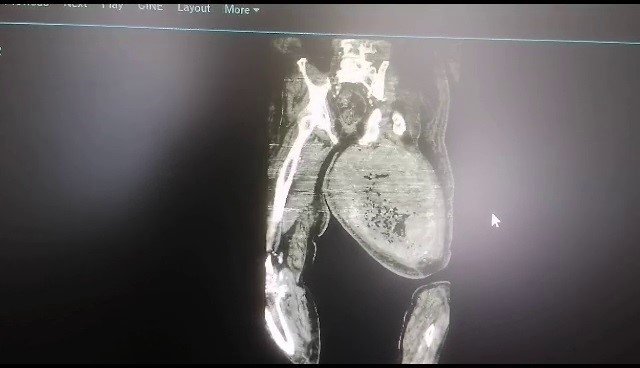

Çorum'da, ayaklarındaki ağrı ve şişlik sebebiyle 4 aydır sağlık sorunları yaşayan Haydar Yatar, Hitit Üniversitesi Erol Olçok Eğitim ve Araştırma Hastanesi'ne başvurdu. Burada yapılan muayenede Yatar'ın ayaklarındaki şişliğin sebebinin tümoral bir kitle olduğu belirlendi. Tıp Fakültesi Ortopedi ve Travmatoloji Anabilim Dalı Başkanı Doç. Dr. Murat Çalbıyık ve ekibi tarafından yapılan 4 saatlik başarılı bir operasyonda Yatar'ın uyluk kemiğinden 8,9 kilo tümör çıkartıldı. Başarılı ameliyat sayesinde 4 aydır çektiği acılardan kurtulan Haydar Yatar, sağlığına kavuştu.

Ortopedi ve Travmatoloji Anabilim Dalı Başkanı Doç. Dr. Murat Çalbıyık da hastanın yaklaşık 4 aydır sağ ve sol uyluk kemiğindeki şişlik şikayetiyle kendilerine başvurduğunu belirterek, "Hasta daha önce bir bypass ameliyatı kalp ameliyatı olduğundan dolayı hastalığın uyluk kemiğindeki şişliğin burada kanamaya bağlı olduğu düşünülmüş. Bize sevk edildiğinde yaptığımız tetkiklerde uyluk bölgesinde 8 kilo 900 gram bir tümör olduğunu tespit ettik. Bu büyük bir tümördü. Tüm damar çevresindeki tümörü çıkararak hastamızı sağılığına kavuşturduk. Hastamızın tüm takiplerini yapıyoruz" diye konuştu.